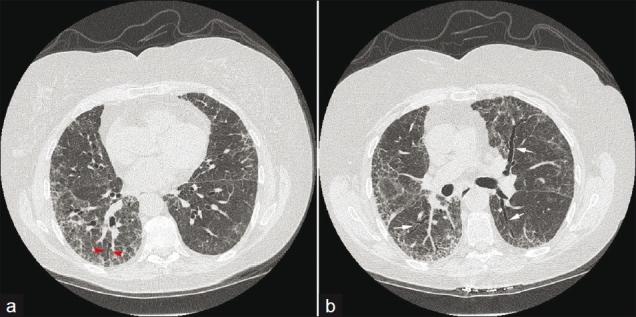

Interstitial lung disease

- Associated with three CT patterns:

- UIP

- NSIP

- organizing pneumonia

UIP

http://www.ncbi.nlm.nih.gov/pmc/articles/PMC3177462/

NSIP

Organizing pneumonia